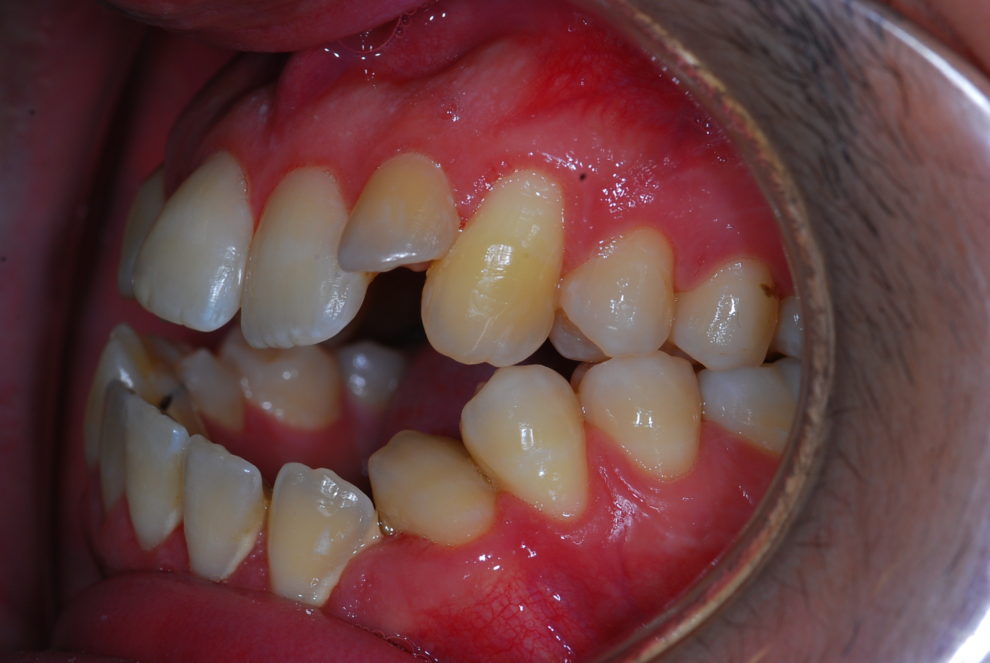

Ortodoncia + Mordida abierta

Nuestro paciente Manuel Vergara Gil acudió a nuestra clínica, y se le hizo una Ortodoncia.